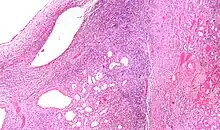

| Micrograph of a cystic nephroma (left of image). Normal kidney is seen on the right. H&E stain. | |

High magnification micrograph of a cystic nephroma showing the characteristic simple epithelium with hobnail morphology, and the ovarian-like stroma. H&E stain.

The characteristics of cystic nephromas are:

- Cysts lined by a simple epithelium with a hobnail morphology, i.e. the nuclei of the cyst lining epithelium bulges into the lumen of the cysts,

- Ovarian-like stroma that has a:

- Spindle cell morphology, and has a

- Basophilic cytoplasm.

Micrograph of a cystic nephroma. H&E stain.